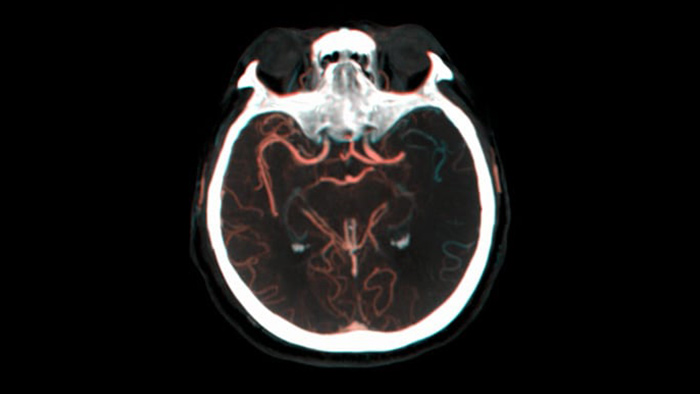

SmartCT Vasoでは、脳梗塞の梗塞部位の全体像を可視化することができる撮影機能です。SmartCT Vasoは、動脈への造影コーンビームCTに高分解能撮影の技術を組み合わせた撮影技術でrestrictive fillingによる梗塞部位の遠位血管も描出することができ、血栓の位置、長さ、梗塞部位の全体像を視覚化できます。3Dロードマップを組み合わせて使用することにより、術中の血栓回収デバイスのナビゲーションも可能となります。